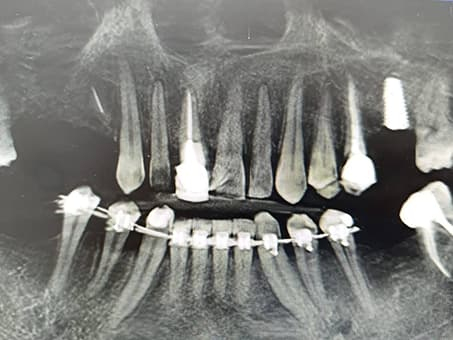

Рентгенография, фото Евродент

Восстановление зубного ряда имплантами